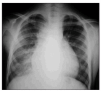

Un año y medio más tarde comienza de nuevo con un cuadro de fiebre, tos productiva, disnea de esfuerzos y leve descenso de la saturación de oxígeno (SaO2) respecto a sus valores habituales. En la auscultación se encontraron crepitantes en hemitórax derecho y en la radiografía de tórax un infiltrado alveolar en base derecha (fig. 1). Mejoró inicialmente con antibióticos, pero sin desaparecer completamente la tos ni la disnea de pequeños esfuerzos, a pesar de tratamiento con broncodilatadores y corticoides.

Figura 1. Radiografía de tórax. Cardiomegalia con infiltrado alveolar en base derecha.